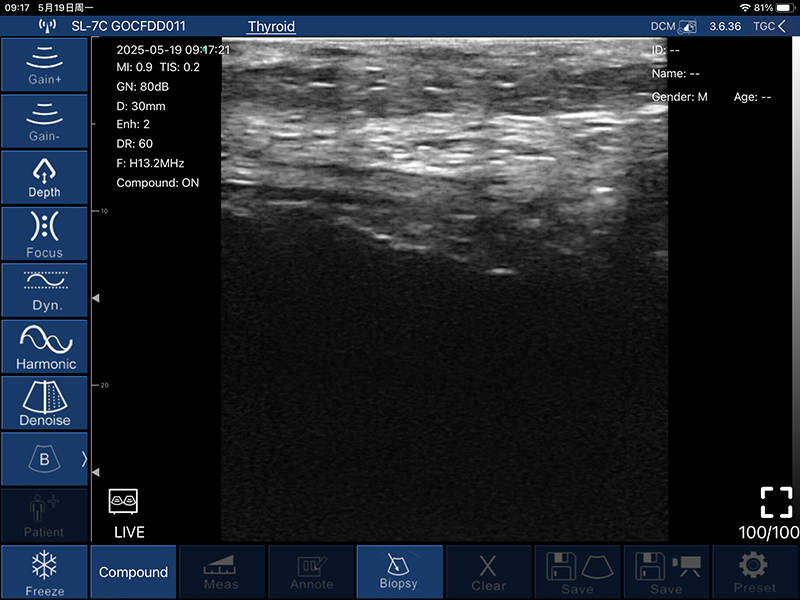

• B模式

增益:30db-105db

降噪:0-1-2-3-4

动态范围: 40-50-60-70-80-90-100-110

• 图像调节:增益、焦点、

反相脉冲谐波、降噪

• 穿刺辅助功能:平面内穿刺引导线功能,平面外穿刺引导与血管自动测量功能